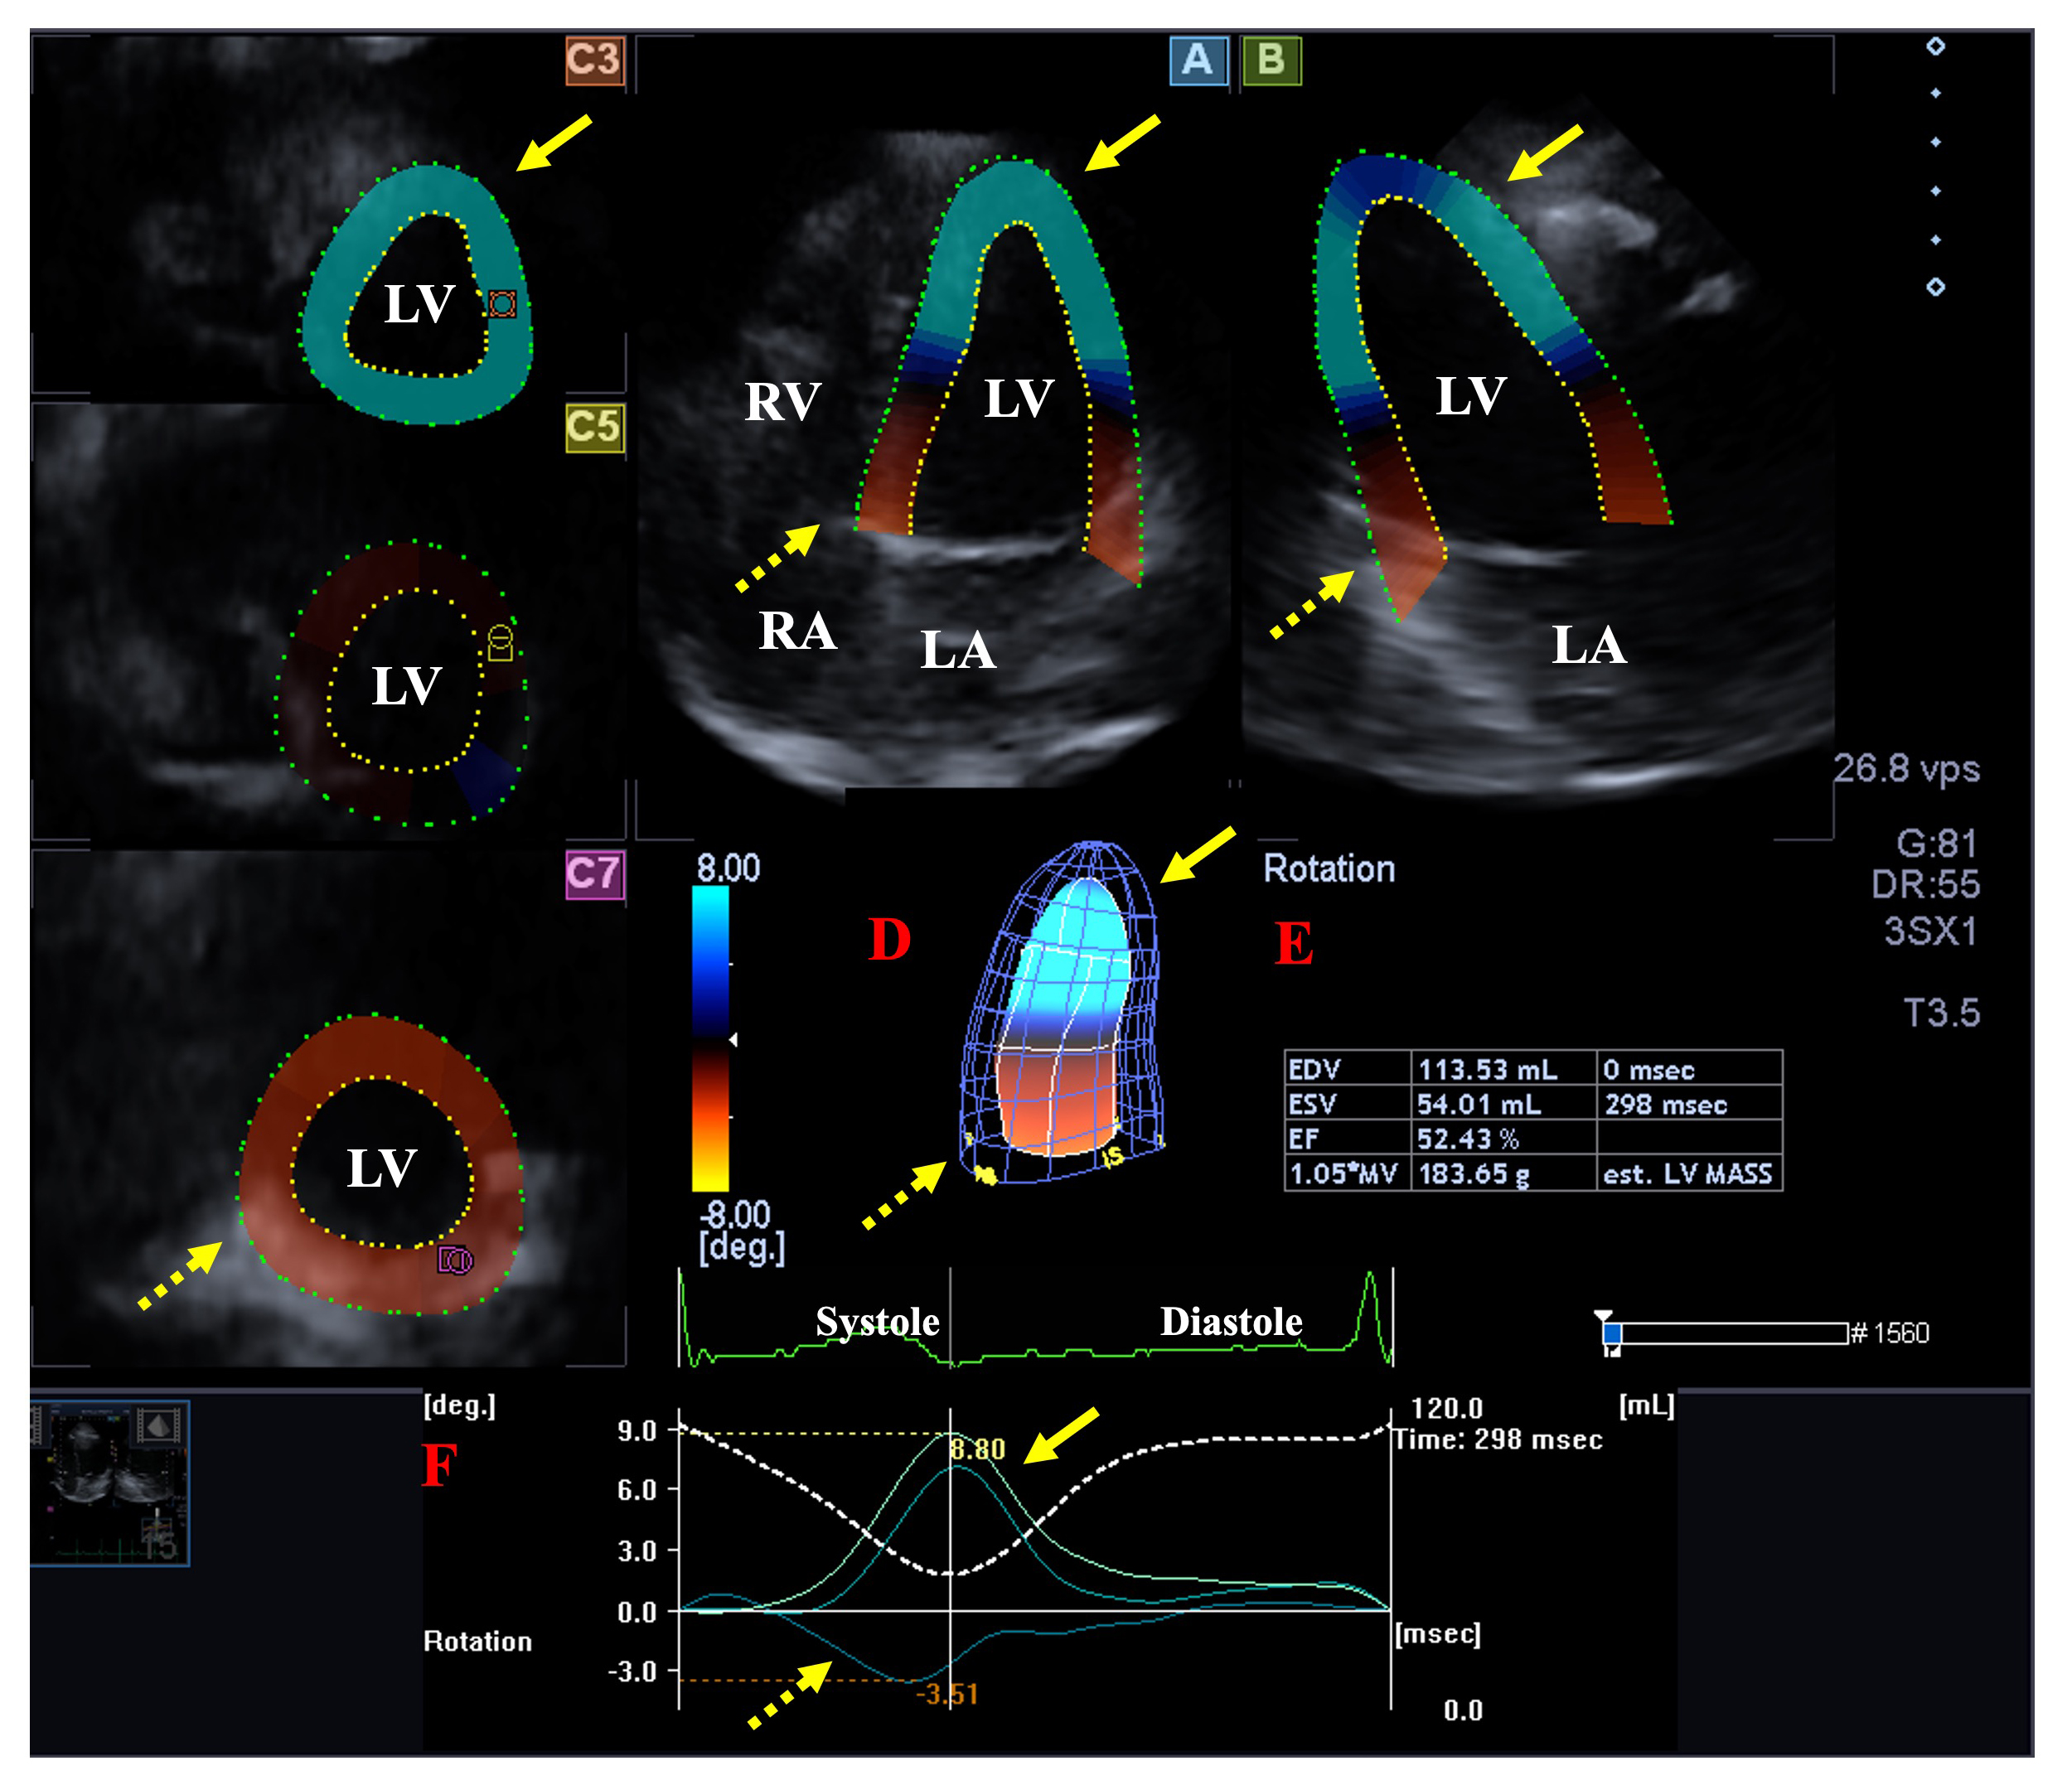

Apical longitudinal 4-chamber (AP4CH) and 2-chamber (AP2CH) views and apical, midventricular and basal cross-sectional planes were automatically selected by the software during analysis. Mitral annular (MA)-LV lateral and septal edges and the endocardial surface of the LV apex were defined. Then a sequential analysis was started to create a virtual 3D cast of the LV helping to determine the following LV rotational parameters using a 3D cast of the LV [17] (Fig. 2):

Fig. 2.

Fig. 2.Analysis of the rotational mechanics of the left ventricle (LV) by three-dimensional (3D) speckle-tracking echocardiography. Apical longitudinal four-chamber (A) and two-chamber views (B) and short-axis views at apical (C3), midventricular (C5) and basal LV levels (C7) are shown together with a 3D model of the LV (D) and calculated LV volumetric data (E). Time - LV apical (yellow arrows) and basal (dashed yellow arrows) rotation curves are shown together with time - LV volume change curve during the cardiac cycle (F). Abbreviations: EDV, end-diastolic volume; ESV, end-systolic volume; EF, ejection fraction; RA, right atrium; RV, right ventricle; LA, left atrium; LV, left ventricle.

- clockwise basal LV rotation (in degrees).

- counterclockwise apical LV rotation (in degrees).

- LV twist (net difference of LV apical and basal rotations in degrees).

- time-to-peak LV twist (in milliseconds).